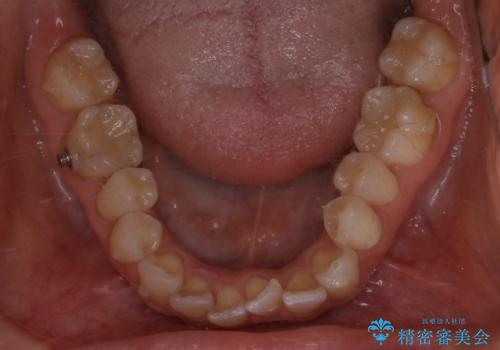

- 下の前歯のがたつきが気になるとの事でご相談にいらした患者様です。

元々はリンガルブラケットをご希望されていましたが、モニター制度を利用してインビザラインによる治療を行いました。

インビザラインFULLで奥歯の噛み合わせから改善させることで、上下の真ん中位置をしっかり合わせることが出来ました。

横顔のシルエットも改善させることができ、大変喜んでいただけました。